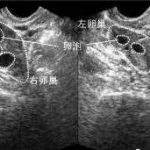

传统的试管婴儿技术只能在体外受精和培养早期胚胎后直接将胚胎移植到子宫内。而三代试管技术则是在体外受精后再将早期胚胎移植到母亲的卵巢内进行继续发育。这种方法可以提高着床率和存活率,减少人工授精失败率。